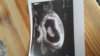

20170428_163621.jpg

• 20170428_163621.jpg

61,6 KB · Wyświetleń: 299

A ja już nie mogę się doczekać 2 Maja i zobaczyć maluszka :)